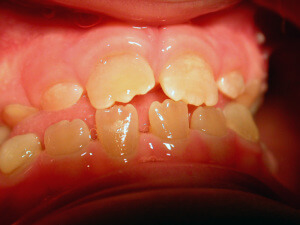

Interceptive Orthodontics

There are ways to prevent orthodontic problems and avoid braces. It’s essential to check our children early and on a regular basis, to avoid teeth crowding, discontinue a bad oral habit, or in order to guide favorably the facial and dentoalveolar development.